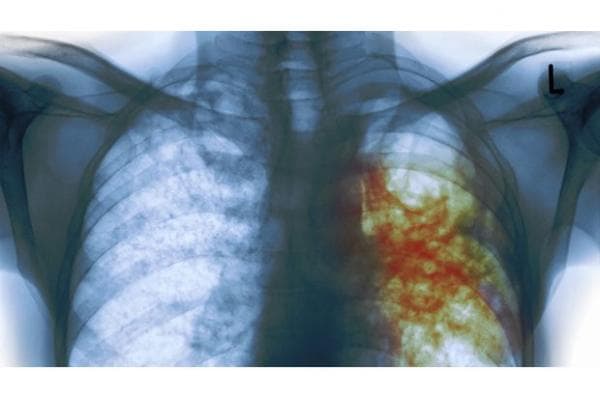

Dahaknya harus diperiksa untuk membuktikan TBC-nya positif atau tidak, resisten obat atau tidak. Kalau negatif bukan berarti tidak TBC, harus foto rontgen melihat kondisi paru-parunya.

Kondisi paru-paru yang terinfeksi TBC berlubang-lubang, ada juga yang ada airnya. Ini yang biasa disebut masyarakat awam sebagai paru-paru basah.